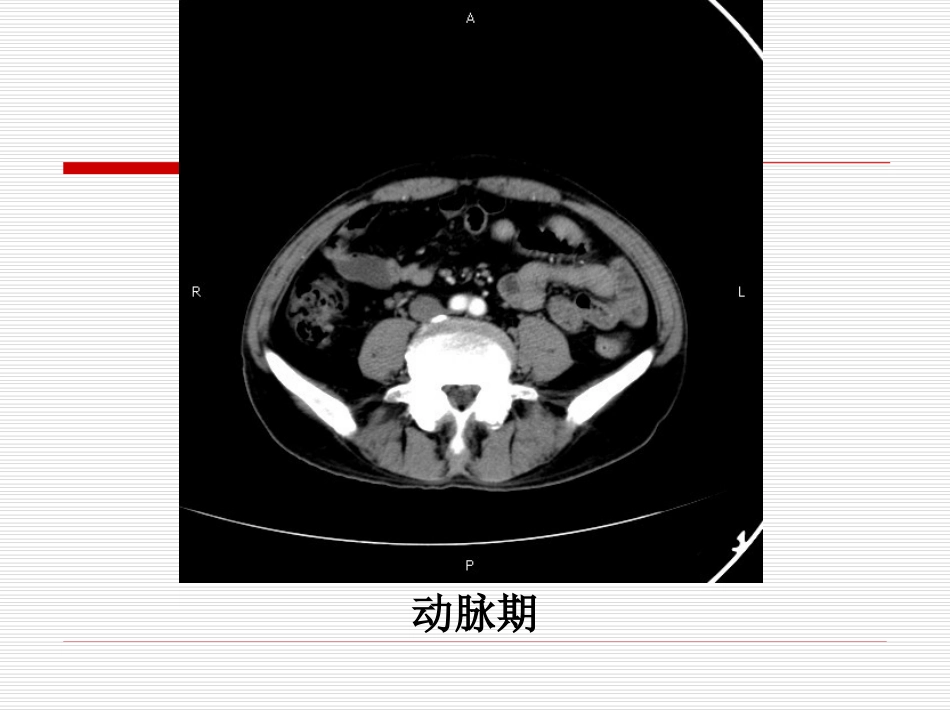

病例讨论2017-5-20李璠患者男,59岁,已婚,农民,于20天前无明显诱因出现黑便,每日一次,柏油样便,伴头晕、心悸、乏力,活动后加重。动脉期门脉期延迟期冠状位矢状位胃镜(胃)胃肠道间质瘤(GIST),部分区域为未分化肉瘤,建议做c-kit基因检测,切缘(-)。免疫组化结果显示:Ki-67(+30%),SMA(-),S-100(部分+),CD34(部分+),CD117(部分+),DOG-1(部分+)。间叶组织的恶性肿瘤统称为肉瘤(sarcoma)。这些肿瘤表现出向某种间叶组织分化的特点。间叶组织包括纤维组织、脂肪、肌肉、血管和淋巴管。骨、软骨组织等。未分化肉瘤是指形态或免疫表型可以确定为肉瘤,但缺乏特定间叶组织分化特征的肉瘤。概述胃肠道间质瘤(gastrointestinalstromaltumor,GIST)是一种遗传学存在频发性C-Kit基因突变、免疫表型上表达C-Kit蛋白(CD117干细胞因子受体)、组织学上富于梭形细胞和上皮样细胞的消化道最常见的间叶源性肿瘤。病理基因表达GIST在遗传学上存在c-kit基因以及血小板源性生长因子受体-α基因的突变;在免疫表型上表达CD117蛋白、CD34蛋白、Nestin巢蛋白、SMA(平滑肌动蛋白)等,其中CD117蛋白、CD34蛋白最常见。CD117蛋白、CD34蛋白表达于肿瘤细胞的细胞膜上。病理组织来源目前认为GIST起源于向胃肠道卡哈尔间质细胞(interstitialcellofCajal,ICC)分化的幼稚间充质细胞;GIST是胃肠道幼稚间充质细胞在分化演变过程中经变异所形成的肿瘤;Cajal细胞是胃肠道细胞中唯一共同表达CD-117和CD34(GIST亦表达CD-117、CD34),同时具有与GIST相同的超微结构的细胞,网膜上亦发现有Cajal细胞。病理发生部位GIST在消化道的发病率从高到低排列依次为胃、空肠、回肠、十二指肠、直肠、结肠、食管,其中发生在胃、小肠和结直肠的GIST约各占60%-70%、25%-30%和5%,食管的发病率<5%。也可发生于腹腔软组织如网膜、肠系膜或腹膜后,胃肠道外间质瘤发病率低。病理大体形态GIST一般单发,少数多发,多发性胃间质瘤预后较差;多发生于胃肠壁的固有肌层,肿瘤可向粘膜和(或)浆膜生长。向粘膜生长的肿瘤可致粘膜溃疡和(或)出血,并可突入腔内。向浆膜生长的肿瘤可突出于浆膜外,有时肿瘤主体在壁外,只有细蒂与胃肠壁相连;切面呈灰白或灰红色质实,可见出血、坏死或囊性变等继发性改变。GIST的细胞形态多样,主要由梭形细胞和上皮样细胞构成;肿瘤细胞排列成束状、栅栏状或漩涡状,间质中可见无定型嗜酸性物沉积;肿瘤中可以发生粘液变性。返回病理图片病理组织学形态病理良恶性标准2000年WHO将GIST分为良性、不确定恶性潜能、恶性三种类型。在确诊的GIST中绝大部分为不确定恶性潜能型;目前多采用的GIST良、恶性判断参考标准:良性,肿瘤<5cm,肿瘤细胞病理核分裂象<5个/50HPF;交界性,肿瘤>5cm,肿瘤细胞病理核分裂象<5个/50HPF;恶性,肿瘤>5cm,肿瘤细胞病理核分裂象>5个/50HPF。临床表现任何年龄段,高发年龄为50-70岁。无性别差异;临床表现:与肿瘤的部位、大小、良恶性等有关。主要表现为呕血、黑便、腹部饱胀不适、腹痛、腹部包块等非特异性症状,消化道梗阻较少见。胃间质瘤CT表现多为单发,少数为多发,形态不一,可呈球形,分叶状;生长方式可分为腔内型、腔外型和腔内外型;大部分呈软组织密度,新鲜出血呈高密度,坏死、囊变区呈低密度;增强扫描病变常呈中度或中度以上渐进性强化,出血、坏死、囊变区不强化,分隔状强化的胃间质瘤多为恶性且预后较差。胃间质瘤(腔内型)胃间质瘤(腔内外型)胃间质瘤(腔外型)胃间质瘤鉴别诊断胃癌胃间质瘤来源胃粘膜上皮细胞胃壁肌层的间充质细胞发病率占胃原发肿瘤的95%占胃原发肿瘤的2%恶性度高良性、交界性、恶性三种类型,恶性度低临床表现胃窦癌可致幽门梗阻消化道出血常见,肠梗阻少见好发部位胃窦部,胃体小弯,贲门胃体部大弯侧,胃底部分型蕈伞型;溃疡型;浸润型腔内型;腔内外型;腔外型胃间质瘤鉴别诊断胃癌胃间质瘤CT表现胃壁局限性增厚为主要表现,首先侵犯粘膜;癌肿与邻近胃壁分界不清,邻近胃壁常增厚;多呈软组织密度,较均匀;明显强化,动脉期强化为主以肿块为主要表...